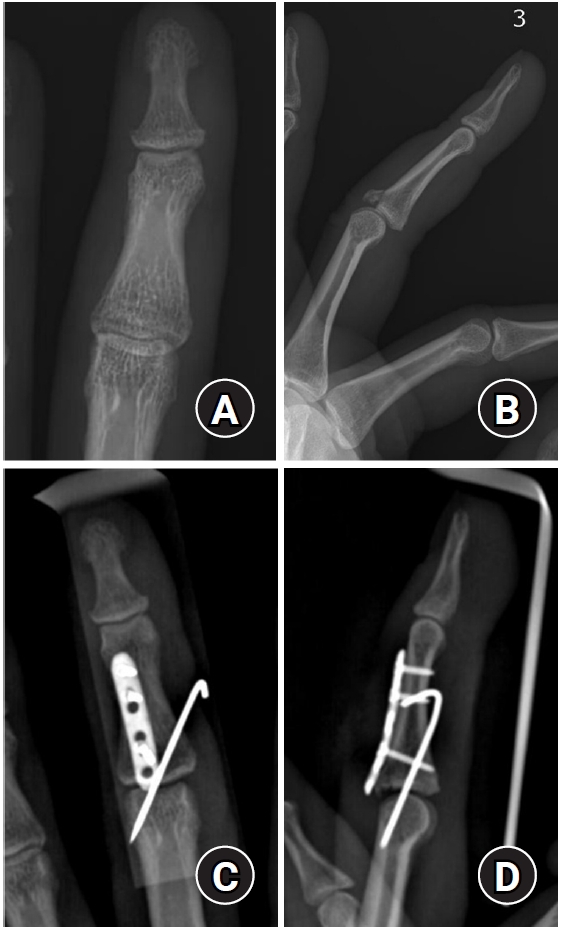

In the case of extraarticular transverse fractures of the proximal phalanx, even if the fracture does not appear severe on X-ray alone, rotational deformity may still be present. Therefore, a diagnosis should not be based solely on X-ray findings, and a thorough physical examination should be performed before surgery to prevent the complication of rotational malunion [9] (Fig. 3).

Fig. 3.

Proximal phalanx fracture of fourth finger with difference between X-ray findings and physical examination. Fracture of the proximal phalanx base of the fourth finger was shown with minimal displacement on the X-ray (A-C). However, finger overlap due to rotational displacement was observed on physical examination (D).

Fig. 3. Proximal phalanx fracture of fourth finger with difference between X-ray findings and physical examination. Fracture of the proximal phalanx base of the fourth finger was shown with minimal displacement on the X-ray (A-C). However, finger overlap due to rotational displacement was observed on physical examination (D).